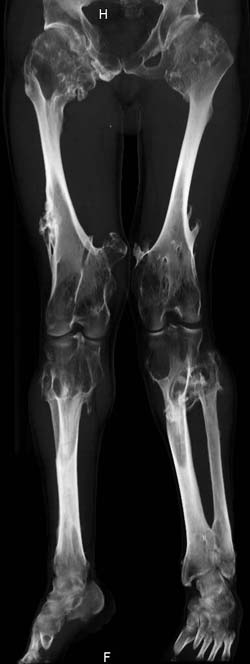

Oбратился больной 30 лет с хондродисплазией, множественными деформациями и экзостозами. Сгибательно-приводящие контрактуры Т/Б сустав, поясничный лордоз.

Интелектуально развит, работает програмистом. Болей нет. Анализы крови в пределах нормы, понижен кальций (общий Ca 1.62, N от 2.3 до 2.75;ионизорованный 0.67, N от 0.7 до 1.07) и щелочная фосфотаза -7.9. По данным КТ, оптическая плотность диафизов 150 - 200 NU (N в его возрасте 300 -350NU) метафизарный остеопороз от 100NU до отрицательных величин - 80 NU.

30 years old male with chondrodysplasia and multiple exostoses admitted.Multilevel deformities, flexion-adduction limitation of hip ROM, lumbar lordosis. Intellectually developed, working in some software company. Painless. Blood tests are normal, except low Calcium (total serum Ca 1. 62, N is 2.3 - 2.75; ionized 0.67 N is 0.7 -1.07) and low alkaline phosphatase 7.9. Diaphysis bone density is about 150 - 200 NU (N in his age is 300 - 350NU). Metaphis osteoporosis is from 100NU to minus 80 NU.

The x-ray is satisfactory for analysis. In The AP view, The knee and ankle should be exactly anterior and the patella should be facing forward, then we can measure the deformity in the AP. Another lateral view of the whole lower limb should be taken, so we can correct 6 dimensions (X, Y and Z axes and Alpha, Beta and Gamma rotation).

But it seemes to me that he has distal femoral valgus and may be also distal tibial. But anyway, we have to measure a good x-ray (lateral distal femoral angle, Medial proximal tibial angle and also the distal tibial angles).

Somtimes there are many deformities in the same lower limb. I do not like to make it sophistacted and correct everything, but just correcting the biggest deformity will make the alignment much better and the patient will be happy with the least risk and least duration of operation.